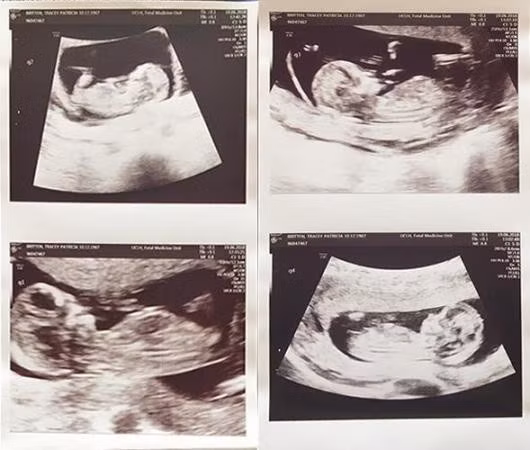

Tracey Britten, 50 tuổi, được đỡ đẻ bởi một đội ngũ 35 nhân viên y, bác sĩ sau khi mang thai 3 con gái và 1 con trai nhờ thụ tinh nhân tạo. Tỷ lệ để một người phụ nữ lớn tuổi như cô mang thai ngần ấy người con là 1/1 triệu người.

Những đứa trẻ được sinh mổ vào tuần thai thứ 31. Cả 3 bé gái và 1 bé trai đều đang được nuôi dưỡng trong phòng chăm sóc đặc biệt, nơi chúng sử dụng ống thở và được truyền chất dinh dưỡng.